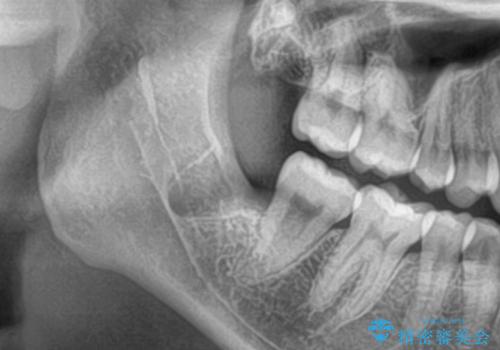

- 親知らずのところが痛く抜きたいとの事で来院。

レントゲン CTを撮影して安全な事を確認して抜歯を行いました。